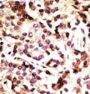

Applikationen WB, IHC-P

IHC-P: 1:50~100